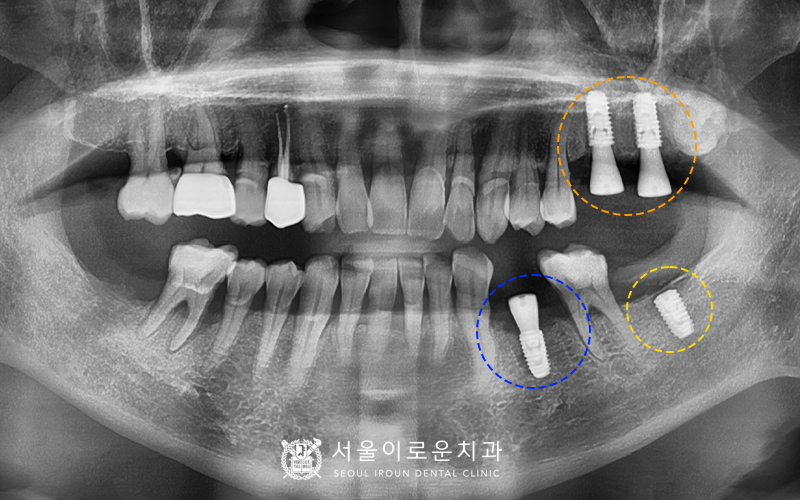

4개의 치아를 발치한 뒤,

뼈이식을 동반한 임플란트를 바로 식립하여

촬영한 x-ray 사진입니다.

기존에 상실되어 없었던

왼쪽 아래 큰 어금니 부위에도

임플란트를 추가로 식립하였습니다. ^^

환.자분의 경우 치주염이 많이 진행된

상태로 잇몸뼈가 상당수 흡수되어

골이식을 동반하였는데요.